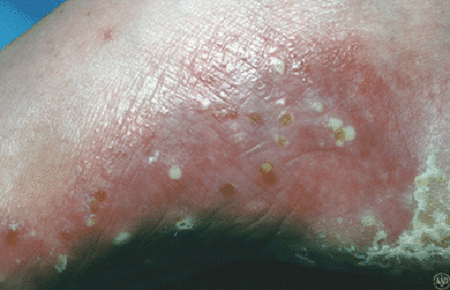

Pustular psoriasis

On their hands and feet, people develop painful pus-filled blisters and thick, scaly skin that cracks easily.